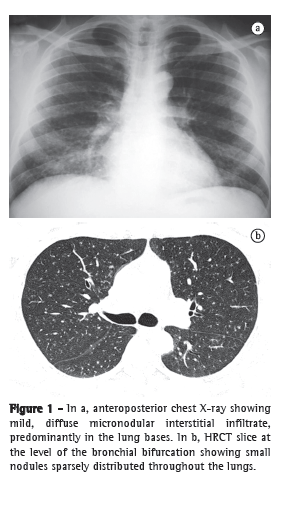

The patient sought treatment at a teaching received antibiotic therapy with amoxicillin (500 mg every 8 h for 7 days). Although the fever subsided and the hemoptysis lessened, the dry cough persisted. He denied other symptoms, such as weight loss, night sweats, and worsening of the overall health status. The patient was referred to the pulmonology department of the hospital for further investigation. Physical examination revealed no significant changes. A chest X-ray revealed mild, diffuse micronodular infiltrate (Figure 1a), which was better characterized by a HRCT scan of the chest (Figure 1b).

The most common radiological finding is alveolar opacity with air bronchogram.(1) Studies based on CT scans have reported the presence of nodular opacities, ground-glass opacities, and small nodules with centrilobular distribution, as well as of the tree-in-bud pattern, findings that are suggestive of a wide range of diseases.(2)